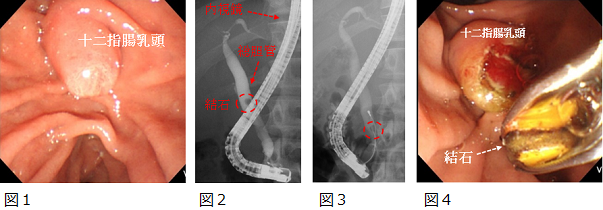

胆膵の治療

内視鏡的逆行性胆管膵管造影:ERCP

肝臓や胆嚢から分泌された胆汁は、総胆管という管を流れて十二指腸に出ていきます。

この総胆管に結石や腫瘍が存在すると、胆汁の流れが悪くなり、胆管に炎症を引き起こすため治療が必要です。

胆管の病変に対しては、内視鏡を用いた処置を行います。

内視鏡を十二指腸まで挿入し、総胆管に処置具を挿入して結石の排石を行ったり、腫瘍の生検や胆汁の流れをよくするドレナージチューブを留置します。

ERCP

図1 十二指腸の総胆管の入り口です(十二指腸乳頭)。

図2 総胆管に処置具を挿入して造影したところです。結石を認めます。

図3 結石を処置具でつかんでいます。

図4 結石を十二指腸に引っ張り出してきたところです。